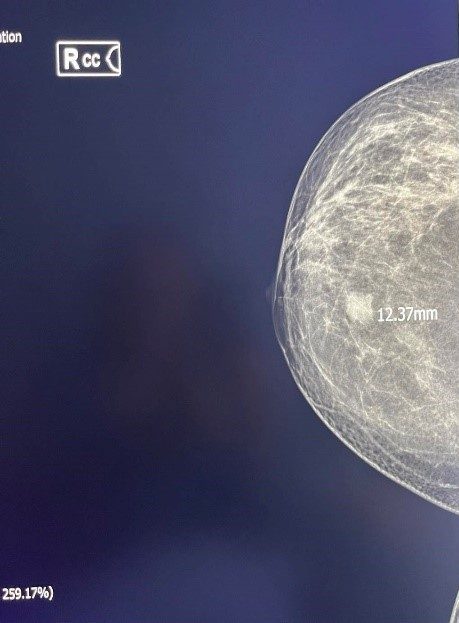

Figure 3. Inv. Intraductal Breast Carcinoma-MG.

Figure 4. Inv. Intraductal Breast Carcinoma (same patient) – Sonoelastography, US